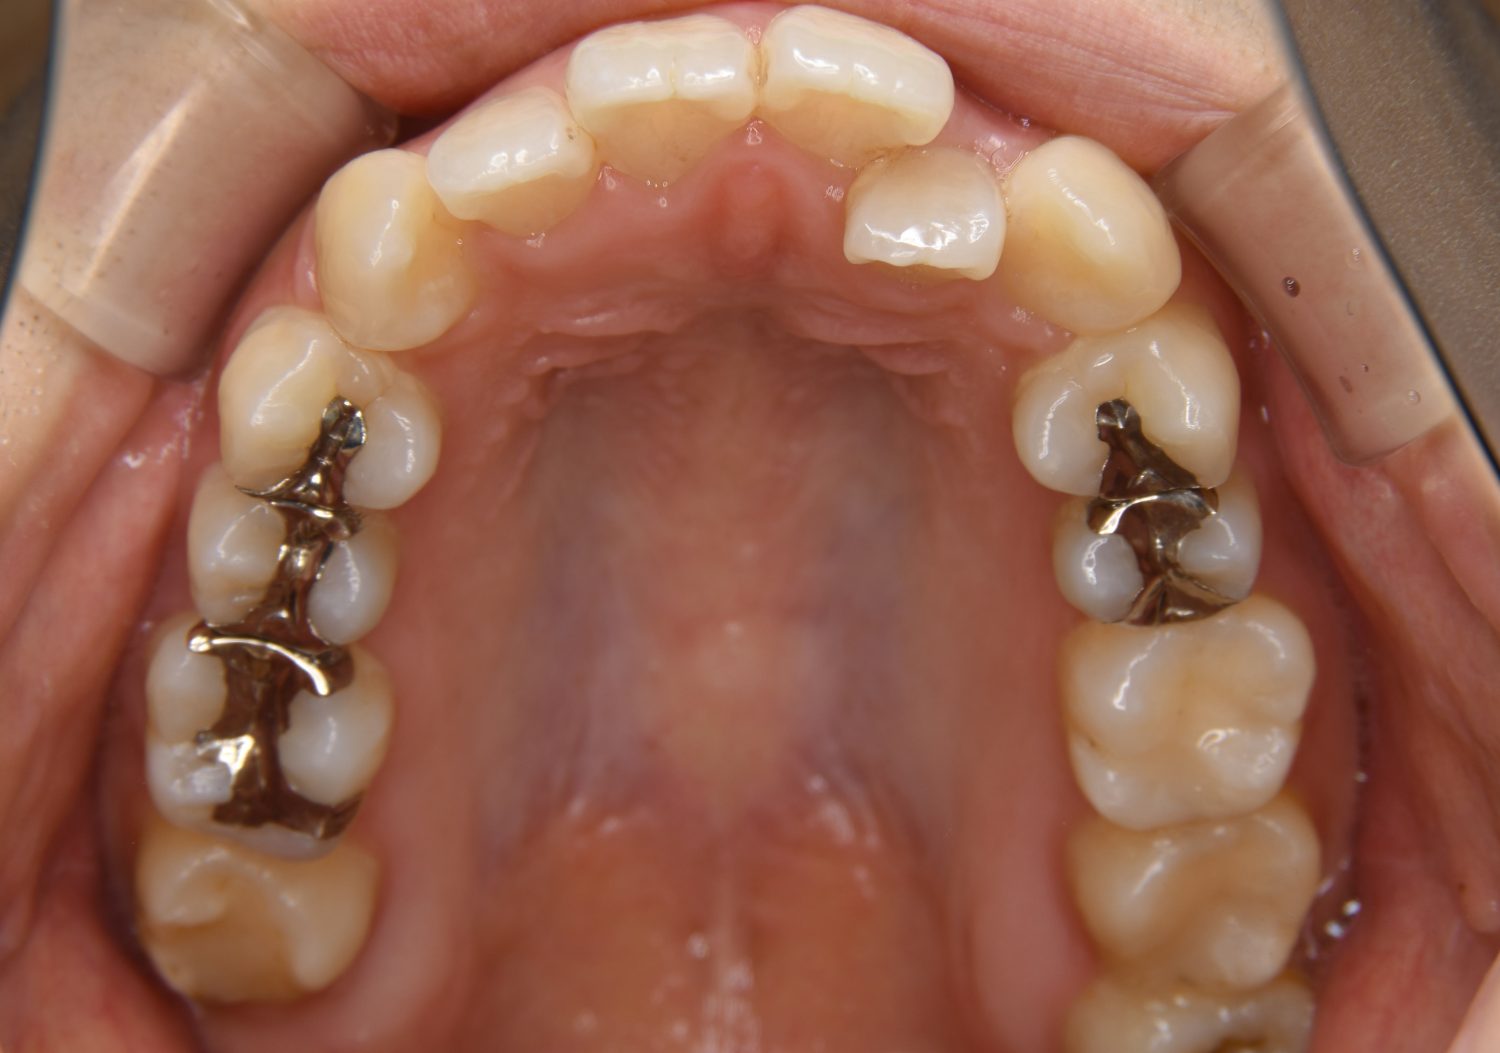

上顎前突の症例紹介①

Before

主訴

上の歯が出ている。歯並び全体が気になる。

治療内容

上顎両側第一小臼歯を抜歯し、上下ラビアルブラケット(唇側装置)に矯正用アンカースクリューを併用し治療を行いました。

上顎前歯の前突により口元の突出が認められました。上の左右の第一小臼歯を抜歯し上顎前歯を後退させることで口元の突出感は改善し、咬合も良好な状態となりました。